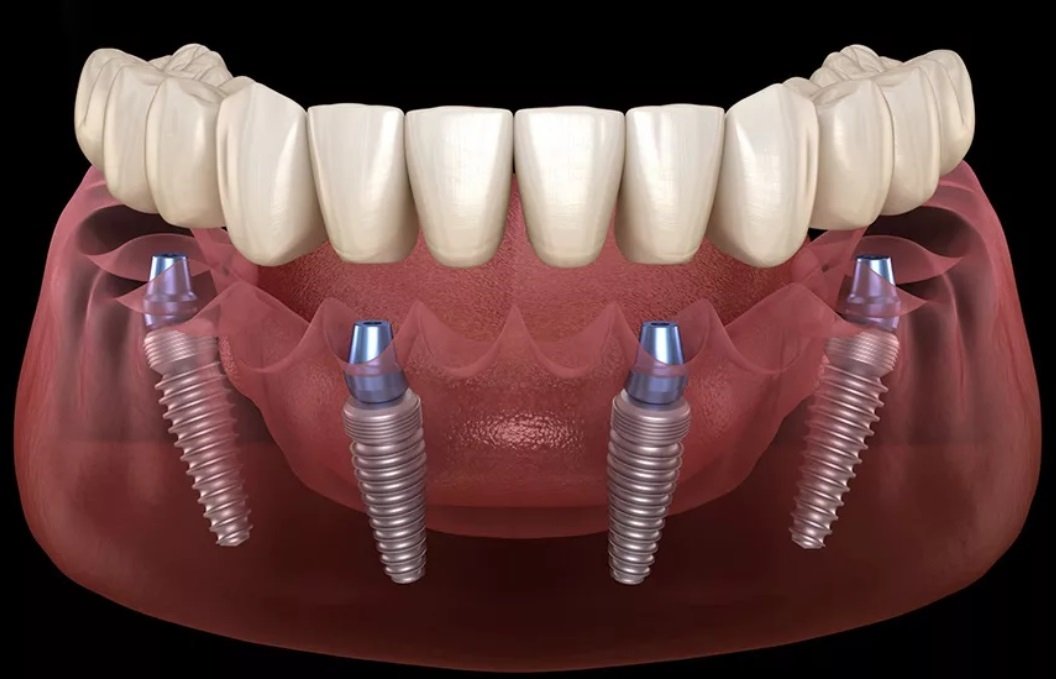

Bunlardan en uygununa karar verildikten sonra çene kemiğine implant yerleştirilir. İmplant tedavisi bir kişinin bir ya da daha fazla dişini kaybettiğinde ve yerine yeni diş yerleştirilmesini istediğinde gerçekleştirilen bir tedavi yöntemidir. Implant diş tedavisi iki aşamadan oluşmaktadır. İmplant tedavisinin süresi yapılacak olan implant sayısına ve hastanın çene kemiğine bağlı olarak yarım saat ile birkaç saat arasında da değişebilir.

İmplant tedavisi ne kadar sürer konusu ise çene kemiğinin durumuna ve yapılan implantın uyumuna göre faklılık gösterir. İmplant operasyonunda kullanılan dikişlerin kendinden erime özelliğine sahip olması tedaviyi bir günde de gerçekleştirme imkanı sunabilmektedir. Bu aşamalarda ise yapılacak olan implant tedavisi eğer ki tek bir operasyon olacak ise bu işlem yine hastanın durumunda göre. İmplant tedavisi cerrahi bir operasyonla yapılmaktadır.

İmplant tedavisinin süresi. Bazı markalar daha hızlı iyileşen modeller üretmiştir ve bu süre uygun vakalarda 20 güne kadar inebilmektedir. Konvansiyonel yaklaşımdacerrahisiden sonra alt çenede 8 hafta üst çenede ise 16 hafta kemik ile vidanın kaynaşması için beklenmelidir. Hekim dişe en uygun implantın hangisi olduğuna karar verir.